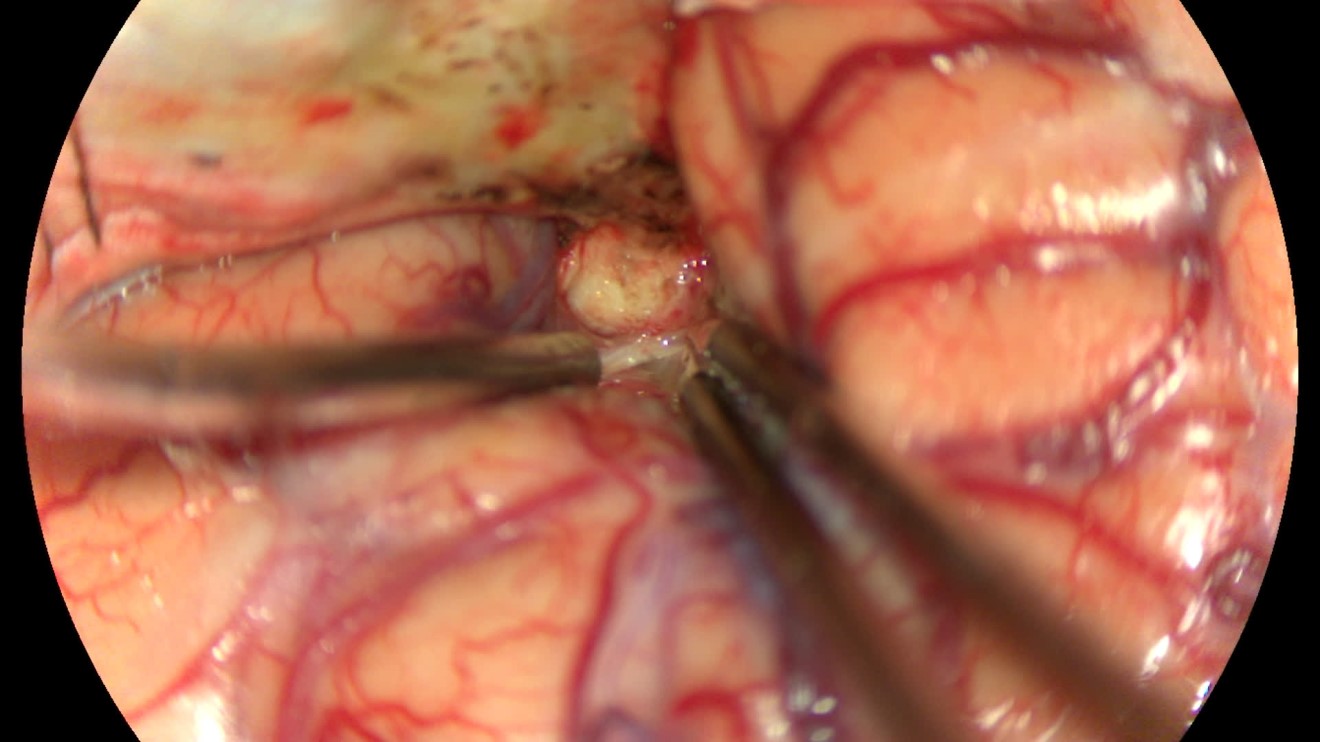

该患者入院后完善常规颅脑影像学检查,左侧颞叶病变,疾病性质不详,转移瘤、胶质瘤、炎症类疾病均不能排除,遂行PET-CT检查,提示左侧颞叶高代谢,淋巴瘤不能排除。组织MDT会诊建议可先行腰椎穿刺查脑脊液脱落细胞学、感染指标,若仍不能确诊,可进一步行开颅病灶切除,术中快速冰冻,根据冰冻结果决定手术手术策略。患者脑脊液脱落细胞学结果:较多淋巴细胞,少许单核细胞及个别中性粒细胞,未见异形细胞,脑脊液常规、生化、脑脊液培养未见细菌生长,诊断仍不能明确,且患者病情进展迅速,患者神志呈昏睡状态,颅脑MRI提示病变较前明显增大(影像学检查间隔两周),且水肿明显加重,遂行开颅病变切除术。术中见部分病变累及蝶骨嵴硬膜,病变质地硬韧,内有多个囊腔,囊内容物为黄色粘稠样脓性物质,留取囊液及实性部分送快速冰冻,在等待冰冻过程中,进一步探查见肿瘤侵犯左侧颞叶,该部位肿瘤质地相对软,无包膜,与周围脑组织无边界,血运不丰富,内有多个囊腔,且肿瘤侵犯侧裂池、颈动脉池,左侧视神经、颈内动脉、大脑中动脉均被病变包绕,且该处肿瘤质地偏硬韧。术中快速冰冻提示组织大片变性坏死,伴胶质增生及淋巴增生。结合病变质地及冰冻结果,考虑为非肿瘤性疾病,可能为炎性病变伴肉芽肿形成可能性大,且肿瘤质地硬韧,累及范围广泛,难以全切,遂行肿瘤大部分切除后结束手术。术后病理结果明确后予以伏立康唑、醋酸卡泊芬净抗真菌治疗。在治疗过程中患者先后出现脑出血、脑梗塞,最终因治疗周期长,花费高、效果不确定等因素,家属放弃治疗,于术后1月去世。